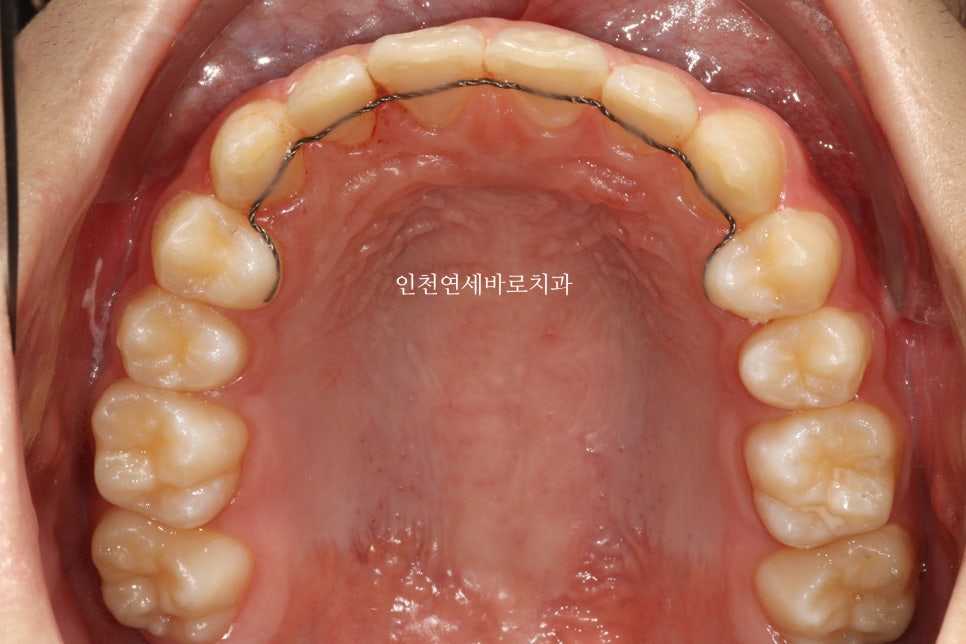

치료 전과 후 입니다.

앞니가 후방이동 한것이 확인됩니다.

우리는 부분교정을 한것이 아니라 간단한 전체교정을 한것입니다.

치료기간 2023.6.20.~2023.12.23.

제작기간 약 1개월

치료기간 약 4개월